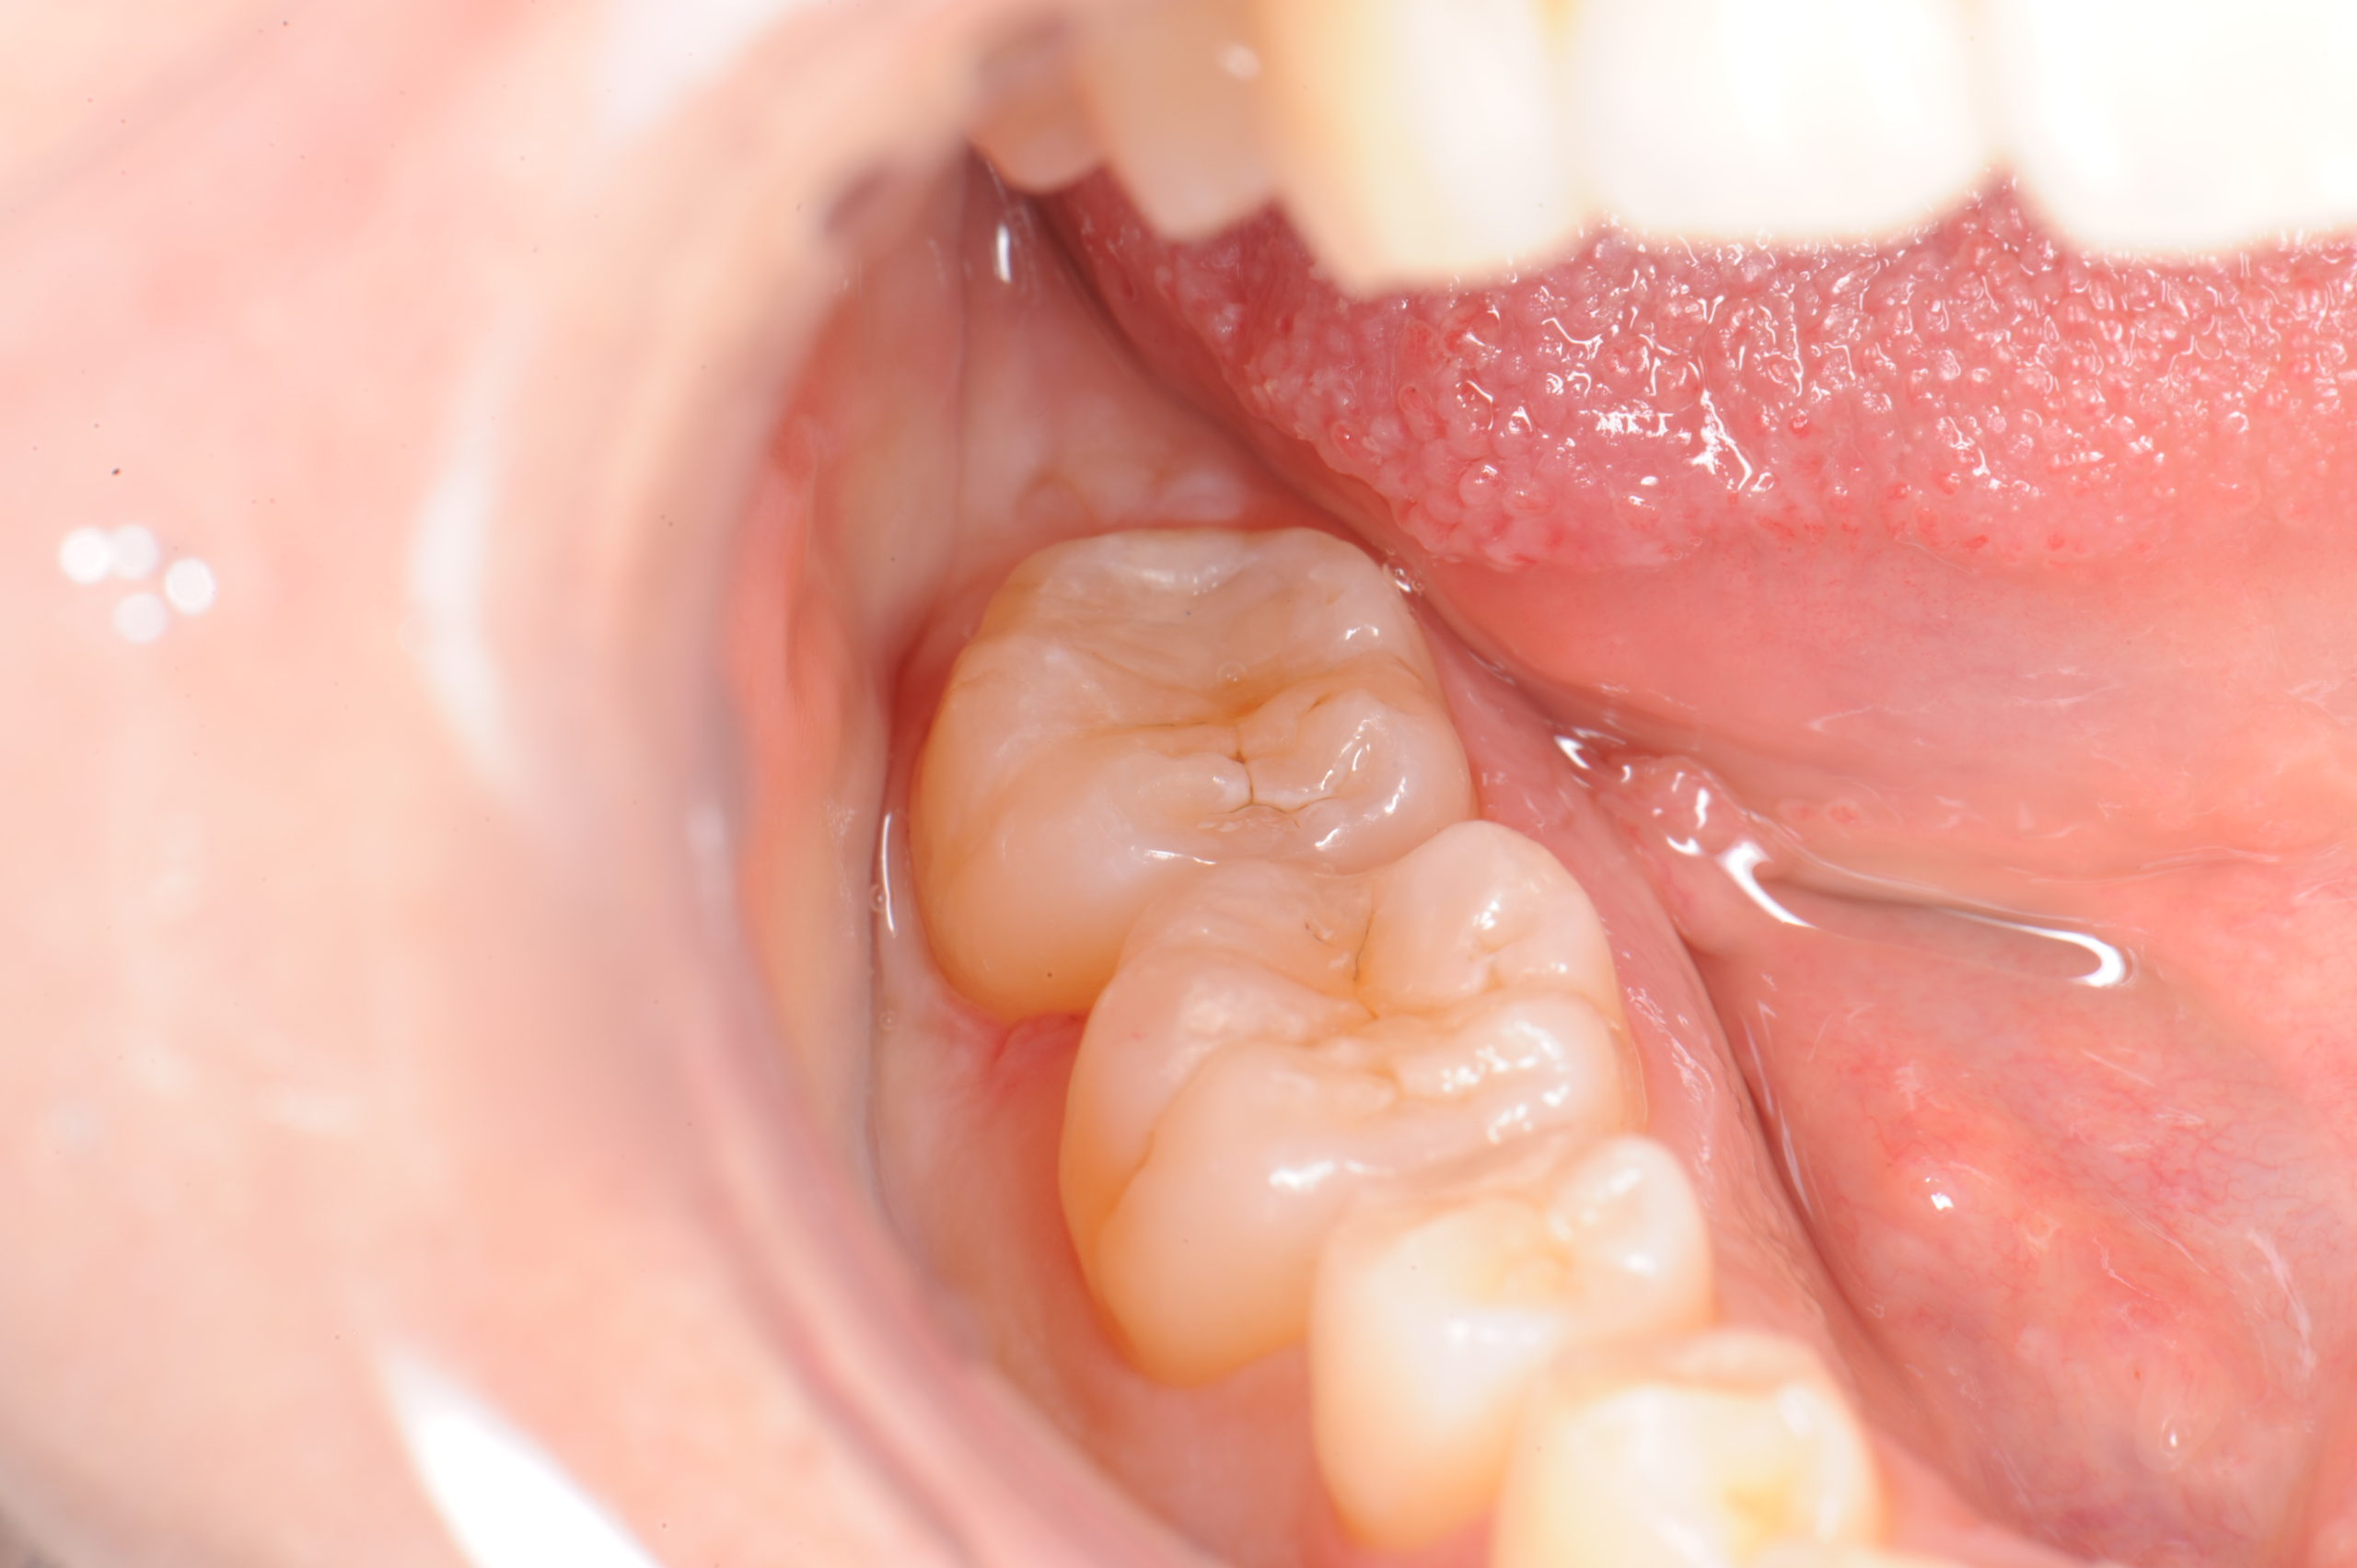

ひび割れた歯の種類

亀裂は次のように現れることがあります。

- クレイジーライン。これは、歯のエナメル質(丈夫な外側の覆い)にできる非常に小さな亀裂です。痛みはなく、治療も必要ありません。

- 骨折した尖端。この種の亀裂は通常、歯の詰め物の周囲で発生します。通常、歯髄(神経、結合組織、血管が存在する歯の中心の柔らかい部分)には影響を与えず、その結果、あまり痛みを引き起こしません。

- 歯肉縁まで広がる亀裂。縦に亀裂が入っていて歯肉縁に達していない歯は、通常は保存可能です。ただし、亀裂が歯肉縁にまで及んでいる場合は、歯を抜かなければならない場合があります。迅速な治療が歯を保存できる最大のチャンスとなります。

- 歯が割れます。これは、表面から歯肉縁の下まで亀裂が入った歯です。実際には 2 つのセグメントに分けることができます。これほど広範な亀裂がある場合、歯全体を保存できる可能性は低いですが、歯科医は歯の一部を保存できる可能性があります。

- 歯根垂直破折。このタイプの亀裂は歯肉線の下から始まり、上に向かって進みます。歯が感染しない限り、多くの場合は症状が現れません。歯を抜かなければならない可能性があります。